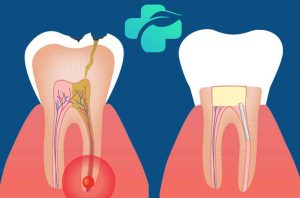

بله، در اکثر موارد، تجربه سطحی از درد دندان بعد از عصب کشی کاملاً طبیعی است. این درد معمولاً خفیف تا متوسط بوده و در نتیجه دستکاری بافت های اطراف دندان و التهاب موقت ناشی از فرآیند درمان ایجاد می شود.

طی درمان ریشه، بافت عفونی یا ملتهب از داخل کانال ها خارج می گردد. این فرآیند می تواند منجر به تحریک بافت های اطراف و استخوان فک شود. لذا، درد بعد از عصب کشی یک واکنش فیزیولوژیک طبیعی به درمان محسوب می شود.

پس از حذف پالپ عفونی، بافت های اطراف ریشه دندان ممکن است دچار التهاب شوند. این التهاب به دلیل دستکاری حین درمان رخ می دهد و معمولاً با گذشت زمان بهبود می یابد.

۴. عفونت باقی مانده یا جدید

در موارد نادر، ممکن است عفونت در کانال های فرعی باقی بماند یا عفونت جدید بروز کند و درد شدید دندان پس از عصب کشی را به همراه داشته باشد.

این حالت اغلب با تورم، تب و درد ضربان دار دندان بعد از عصب کشی همراه است و نیاز به بررسی مجدد دندانپزشک دارد. تشخیص و درمان به موقع حیاتی است.

۳. پرفوراسیون (سوراخ شدن) ریشه

در حین عصب کشی، ممکن است دیواره ریشه سوراخ شود. این پرفوراسیون مسیری برای نفوذ باکتری ها ایجاد کرده و منجر به التهاب و درد دندان بعد از عصب کشی می شود.

درمان پرفوراسیون با استفاده از مواد خاصی برای مهر و موم کردن سوراخ انجام می شود. عدم درمان صحیح می تواند به درد دائمی بعد از عصب کشی منجر شود.